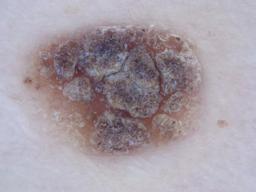

{

"age_approx": 60,

"anatom_site_general": "head/neck",

"concomitant_biopsy": true,

"diagnosis_1": "Benign",

"diagnosis_2": "Benign melanocytic proliferations",

"diagnosis_3": "Nevus",

"diagnosis_confirm_type": "histopathology",

"image_type": "dermoscopic",

"lesion_id": "IL_4655248",

"melanocytic": true,

"sex": "female"